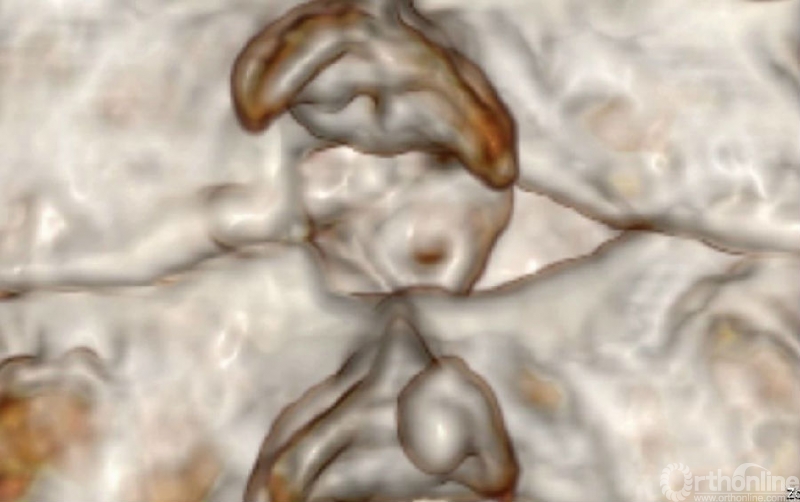

入院查体患者四肢肌张力高,双侧hoffman阳性。CT及MRI检查提示C4/5左侧关节突内缘有一巨大骨块(15mm*16mm),相应节段椎管严重狭窄。椎管内骨块的前端还有一游离骨块。

影像学资料